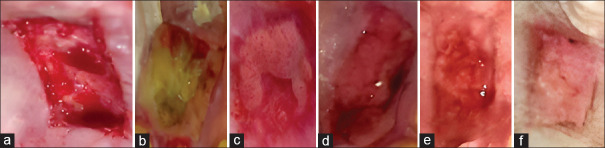

Aim: The present study aimed to compare and assess the wound healing efficacy of topically applied ozonated oil in palatal wounds following a free gingival graft (FGG) procedure.

Materials and methods: A total of 10 patients were selected and randomly assigned to control or test groups. FGG surgery was carried out on all the patients. In the test group, the patients received ozonated oil of 14 μg/mL concentration at the donor site. In the control group, the patients were not treated with ozonated oil and received only stent at the donor site. The primary outcomes calculated were postoperative pain (Visual Analog Scale) and wound healing index (Landry et al.), and the secondary outcome calculated was wound size for up to 28 days.

Conclusion: These results suggest that topical ozonated oil application on palatal wounds following FGG harvesting enhances tissue healing in terms of epithelialization and wound size reduction and also reduces postoperative discomfort.